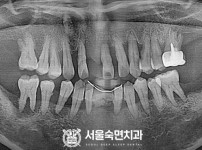

임플란트-전후사진4

임플란트-전후사진5